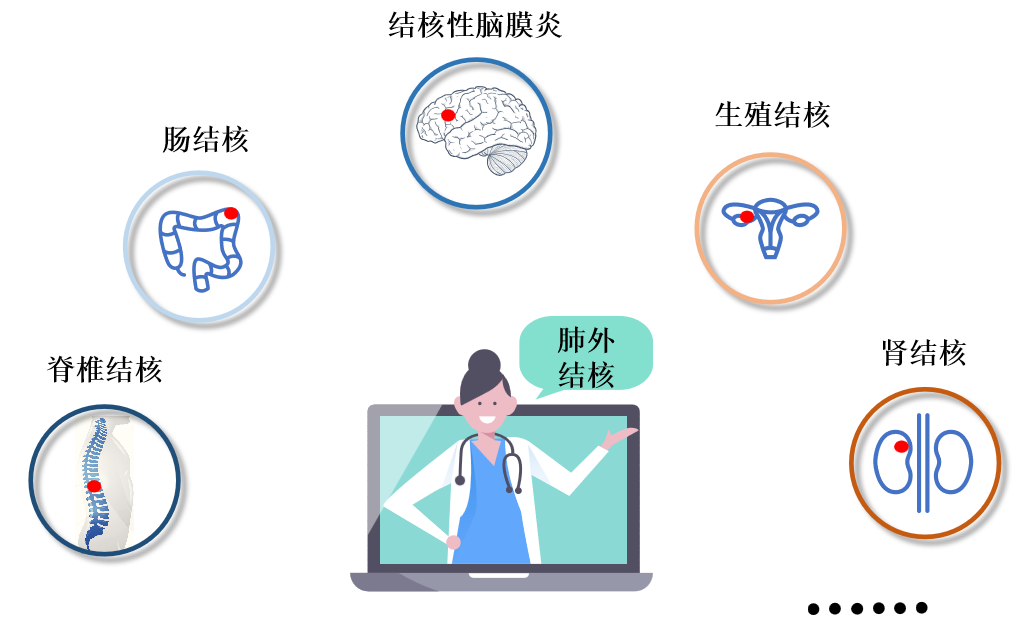

з»“ж ёз—…еҜ№дёӘдҪ“зҡ„еҚұе®і-иӮәеӨ–з»“ж ёиӮәеӨ–з»“ж ёеӣ з—ҮзҠ¶дёҚе…ёиҢғ�пјҢ�пјҢпјҢйҖҡеёёзЎ®иҜҠиҫғжҷҡ�пјҢ�пјҢпјҢеҜ№з»„з»ҮеҷЁе®ҳйҖ жҲҗдёҖе®ҡзҡ„жҚҹе®і�гҖӮгҖӮеҰӮи„Ҡжҹұ/йӘЁжһўзәҪз»“ж ё�пјҢ�пјҢпјҢеҸҜд»ҘеҜјиҮҙжӮЈиҖ…з•ёеҪў�пјӣ�пјӣз»“ж ёжҖ§и„‘иҶңзӮҺеҸҜйҖ жҲҗз—…дәәж®’е‘Ҫ�пјӣ�пјӣиӮҫз»“ж ёеҸҜд»ҘеҜјиҮҙиӮҫеҠҹж•ҲеҸ—жҚҹ�пјӣ�пјӣз”ҹж®–еҷЁе®ҳз»“ж ёеҸҜд»ҘеҜјиҮҙдёҚеӯ•дёҚиӮІзӯүзӯү�пјҢ�пјҢпјҢиӮәеӨ–з»“ж ёдёҘйҮҚжҚҹе®іжӮЈиҖ…иә«еҝғеә·еҒҘ�гҖӮгҖӮ